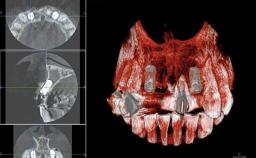

Replacement of Four Incisors with a Fixed Partial Denture on Two Narrow-Neck Implants after Implant Failure

| Jaw | Maxilla |

| Area | Anterior |

| # of Implants | 2 |

| Bone Augmentation | Horizontal|Staged|Vertical |

| Bone Volume | Deficient vertically or deficient vertically AND horizontally |